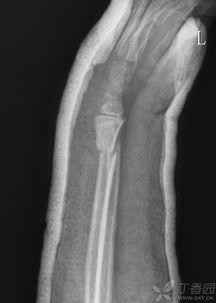

首先,让我们来了解一下什么是骨科手法复位。骨科手法复位,顾名思义,就是通过医生或专业人士的手法,对骨折、脱臼等骨科疾病进行复位的一种治疗方法。这种方法不仅能够减轻患者的痛苦,还能在一定程度上避免手术的风险。